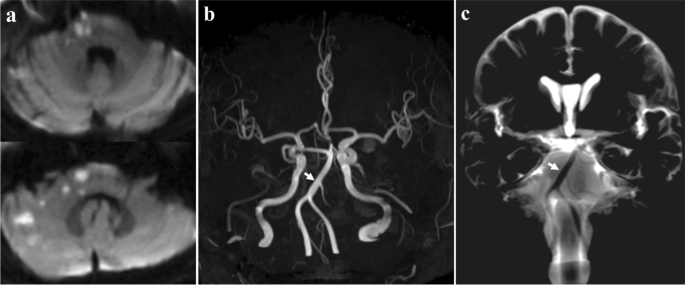

Case 2

A 64-year-old male patient with hypertension presented with vertigo, left peripheral facial palsy and left ataxia. DWI revealed left AICA territorial infarction (left inferolateral pons, brachium pontis, superior cerebellum) (Fig. 2a). On MRA, the left AICA was absent, while the right AICA was visualized clearly (Fig. 2b). BPAS-MRI showed normal bilateral AICA (Fig. 2c). Therefore, the radiological diagnosis of the left AICA occlusion was made, and left AICA was the victim vessel of this infarction.

Diffusion-weighted image revealed left anterior inferior cerebellar artery (AICA) territorial infarction (a).On magnetic resonance angiography, the left AICA was absent, while the right AICA was visualized clearly (b). Basi-parallel anatomic scanning magnetic resonance imaging (BPAS MRI) showed normal bilateral AICA (c)

Case 3

A 60-year-old male patient presented with vertigo and right ataxia. The DWI showed acute infarction involving right inferolateral pons, brachium pontis and superior cerebellum (Fig. 3a). The right AICA was absent on MRA (Fig. 3b) and BPAS-MRI (Fig. 3c). The comprehensive diagnosis was considered as right AICA congenital aplasia, and other causes of the infarction needed to be explored. Finally, a proximal atrial fibrillation was found through long-term monitoring, and the cardiac embolism was presumed as the etiology of infarction.

The diffusion-weighted image showed hyperintensity lesions in right inferolateral pons, brachium pontis and superior cerebellum (a). The right anterior inferior cerebellar artery (AICA) was absent on magnetic resonance angiography (b) and basi-parallel anatomic scanning magnetic resonance imaging (BPAS-MRI) (c)